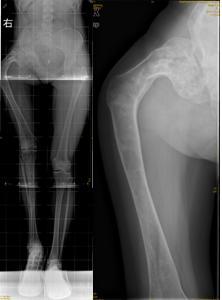

对于严重髋内翻畸形颈干角<60°,且股骨头下方有骨赘形成(如图1),肢体短缩严重者:如果继续使用DHS钢板,力求使颈干角恢复到120°时,此时髋关节头臼咬合已不匹配,臀中肌张力会更大,甚至肢体延长过多会引起坐骨神经症状。对这类患者我们采用DCS钢板,缩减颈干角为95-105°,术后患者髋关节头臼咬合基本匹配,臀中肌经轻度松解也可适应,同时也减少了坐骨神经损伤的风险。26例中我们使用DCS钢板6例,术后均达到满意的效果。

图1女性,18岁,术前肢体短缩9cm图2 术后力线纠正

图3 术后肢体等长

图4 女性,17岁,术前肢体短缩4cm图5 术后2年复查肢体等长,截骨处愈合